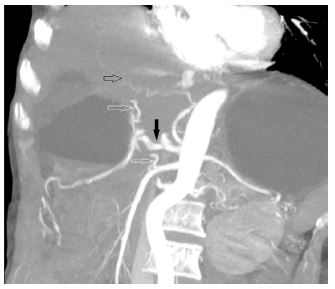

Variance in the origin of CHA was seen in 7 patients (origin of CHA from SMA in 2 and aorta in 5 patients). Normal origin of RHA from Hepatic Artery Proper (HAP) was seen in 361 patients. Replaced origin of RHA was seen in 63 % of total variants (commonest variant) while the accessory origin of RHA was seen in 1 (3.5%) case. Replaced LHA origin was seen in 3 (Figure 4) (10%) cases and accessory LHA origin in two (6.5%) cases.

Figure 4: Oblique CT reformats showing replaced LHA (black open arrow) from LGA and accessory RHA (lower white open arrow) from SMA. The hepatic artery (Black arrow) and Right hepatic artery (Upper white open arrow) are also seen.